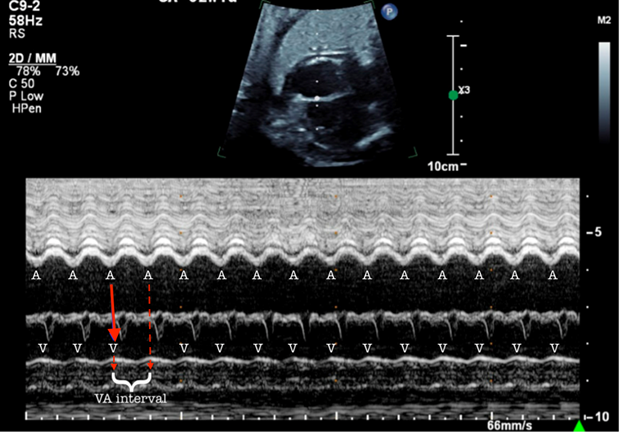

Figure 3: M‐Mode Tracing Through the RA and RV From a Four‐Chamber Image Demonstrates a 1:1 VA Relationship

Figure 3: M‐Mode Tracing Through the RA and RV From a Four‐Chamber Image Demonstrates a 1:1 VA Relationship. Courtesy of Ramachandra R, Ho DY.

The interval between the V and A (the VA interval) is long.

A = atrial contraction; RA = right atrium; RV = right ventricle; V = ventricular contraction; VA = ventriculoatrial.

Figures 1 and 2 demonstrate a 1:1 atrial-ventricular (A-V) relationship, with one ventricular contraction for every atrial contraction and a short ventriculoatrial (VA) interval. Labeled versions of the images are shown in Figures 3 and 4. This fetus most likely had a re-entrant supraventricular tachycardia (SVT), which typically has a rate between 220 and 300 bpm and a 1:1 A-V relationship with a short VA interval (Figure 3). In contrast, ectopic atrial tachycardia, permanent junctional reciprocating tachycardia, and sinus tachycardia have a 1:1 A-V relationship with a long VA interval. In the setting of atrial flutter (AFL), atrial rates are typically 350-500 bpm with consistent or varying rates of atrioventricular (AV) block (2:1, 3:1, or 4:1). The resultant ventricular HRs are a proportional fraction of the atrial rate.